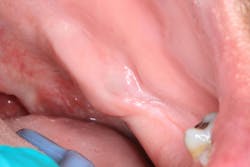

Clinical assessment reveals a fluctuant mass that is tender to palpation on the lingual side of the left mandibular jaw, inferior and lingual to where no. 17 would be, along the palatoglossal arch muscle. The size of the mass is approximately 12 mm x 24 mm, the tissue in the surrounding area is normal in color, and there is no opposing dentition or history of trauma to the area (figures 1 and 2).